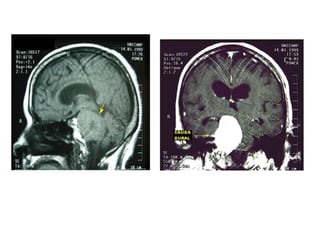

Craniofaringioma(imagem)

• Rx de crânio

– 50%

– 54 a 96% - calcificações suprasselares

• TC

– Calcificações, caráter cístico da lesão e

hiperatenuação após injeção de contraste

– Hipodensa

• RM

– Estabelece os limites e as relações da

lesão(hipotálamo, quiasma e III ventrículo)

– Limites da zona de gliose peritumoral e córtex

– Hiperintensa em T2 e intensidade variável em T1

Azul – dilatação ventricular

Amarela – cisto

Vermelho - sólida